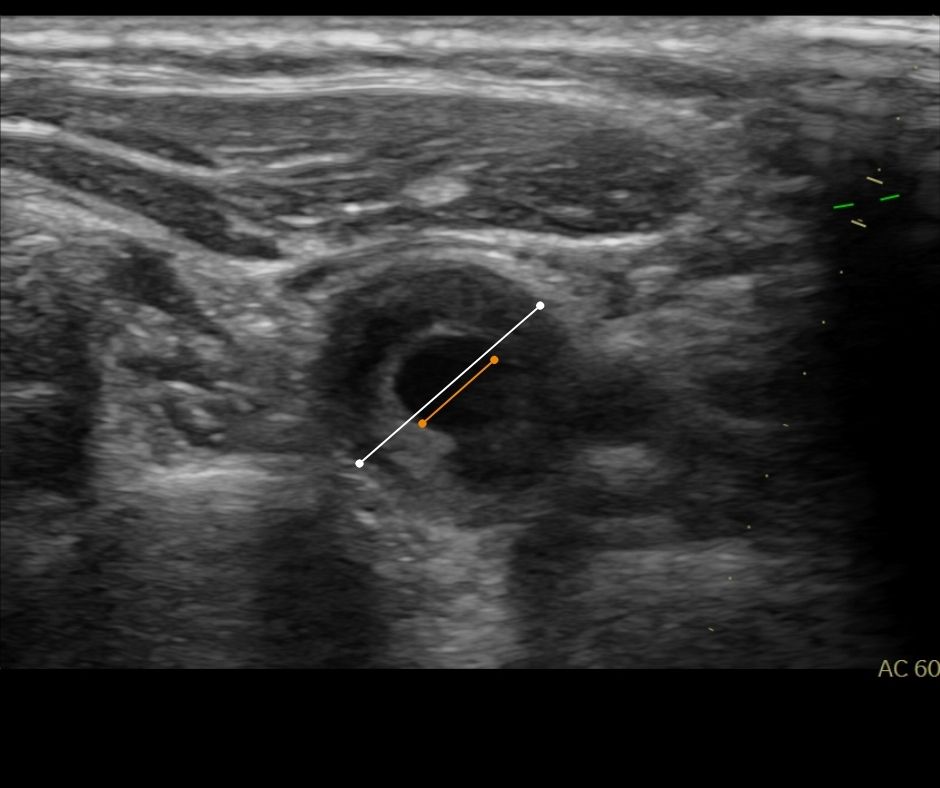

Bildnachweis einer Verengung der Halsschlagader mit weichem Plaquematerial

Bei der auf die Anamnese folgenden Sonographie der Halsschlagadern dokumentierte die abgebildete Stenosemorphologie eine Verengung der Halsschlagadern, eine Karotisstenose.

Mit Hilfe des Gefäßultraschalles lassen sich nicht nur Strömungsverhältnisse in den Gefäßen messen, sondern es gelingt mit hoher Genauigkeit, bereits frühmanifestierte (arteriosklerotische) Veränderungen des Gefäßbettes zu erkennen UND es ermöglicht eine Beurteilung der sogenannten Plaquemorphologie (Zusammensetzung des Plaques). Diese ist unabdingbar in der Beurteilung eines erhöhten Embolierisikos.